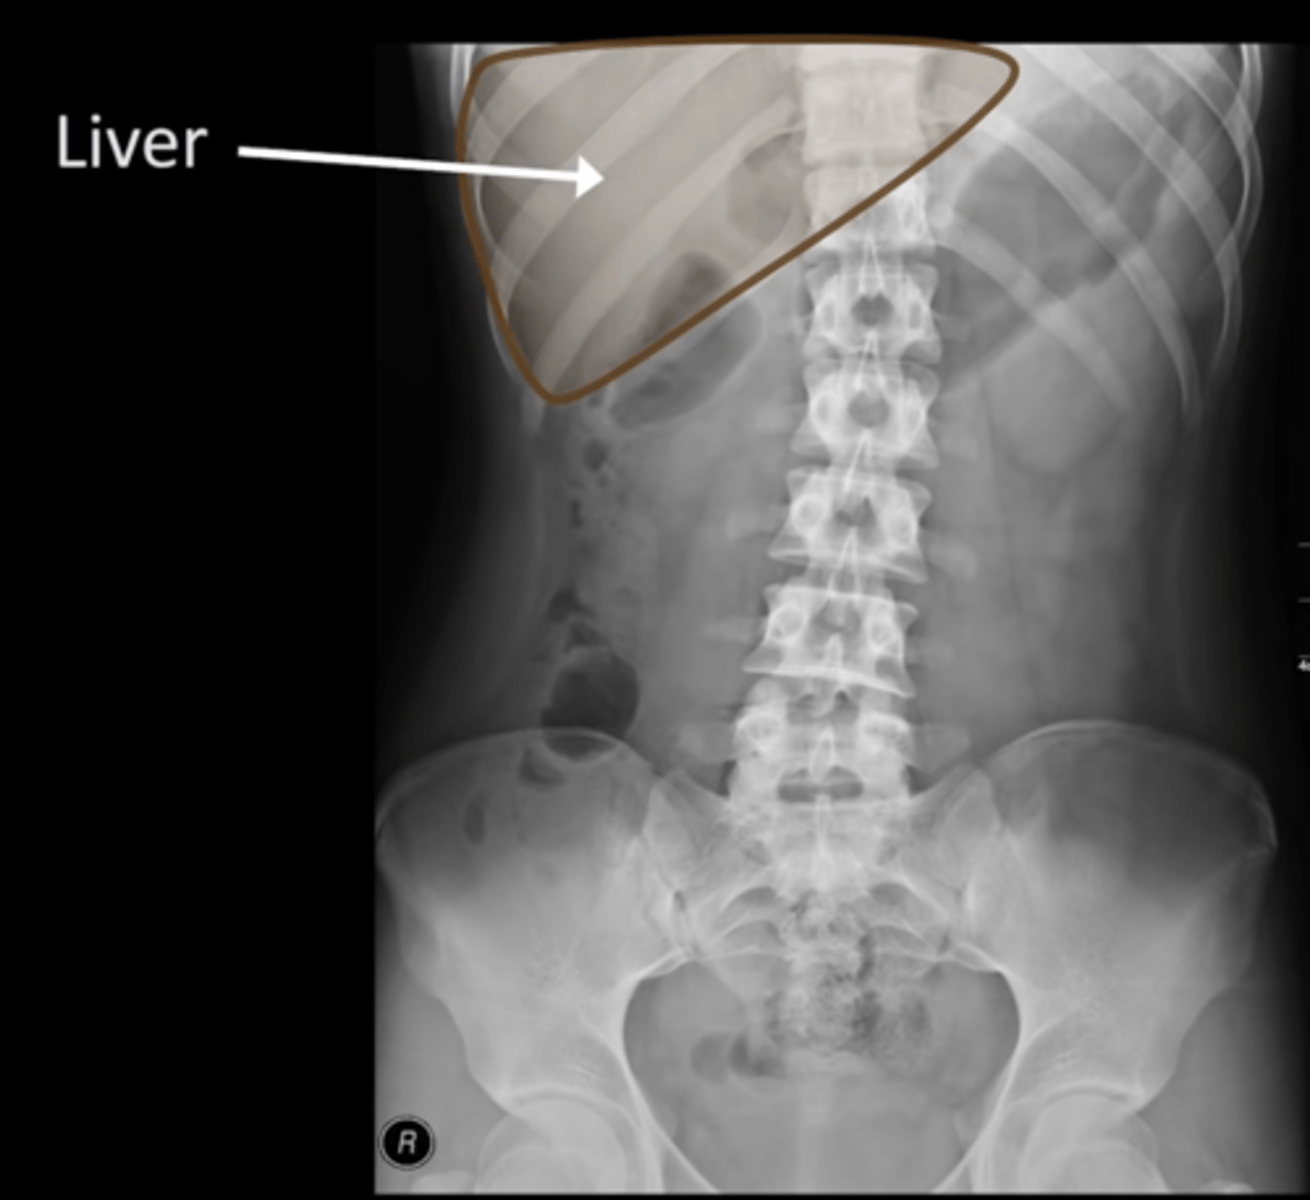

Normal AXR (and normal size liver)

Hepatomegaly

Hepatomegaly (pic 2)